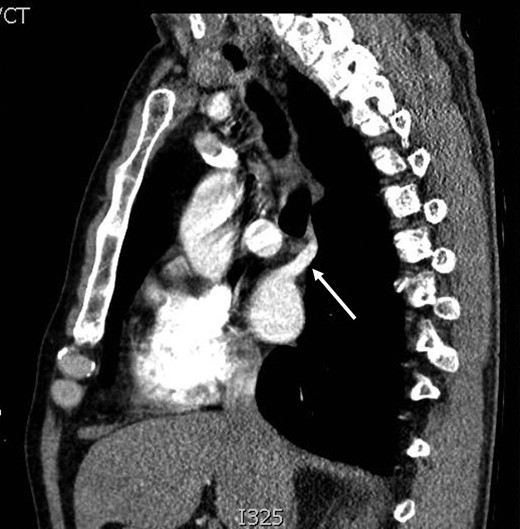

During discussions at the multidisciplinary team meeting, the computed tomography scans of his thorax were reviewed by our radiology colleagues and an anomalous right upper lobe vein was identified.

The patient underwent a right postero-lateral thoracotomy. The right upper lobe pulmonary artery and vein were identified and divided with vascular Endo GIA™ staples. Lymphadenectomy was performed in the draining lymph nodes and we proceeded to isolate the upper lobe bronchus. Prior knowledge of an anomalous venous drainage of the upper lobe made us adopt a cautious approach during dissection posterior to the right upper lobe bronchus and a vascular structure was identified that could be traced in the left atrium; thus, it was found to be an anomalous upper lobe pulmonary vein. The anomalous vein was divided with vascular Endo GIA™ staples. The bronchus was divided with a TA™ stapler.

The patient recovered well postoperatively and was discharged home. Histologically, the patient's tumour stage was pT1aN0 (Figs 1–6).